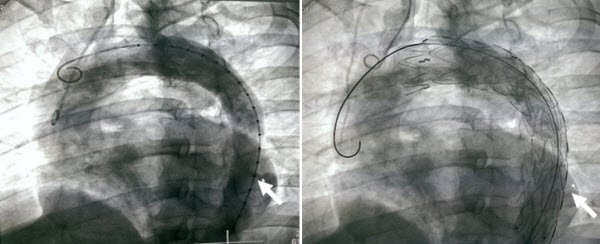

Hình ảnh trước và sau khi đặt stent graft động mạch chủ

Ngày 28/8/2017, các bác sĩ Trung tâm Phẫu thuật Tim mạch và lồng ngực – Bệnh viện Hữu nghị Việt Đức đã quyết định dùng phương pháp can thiệp stent graft động mạch chủ, đặt stent trong lòng can thiệp nội mạch.

Đây là một giải pháp hạn chế rủi ro, do thủ thuật đơn giản hơn so với mổ mở, người bệnh hầu như không bị mất máu trong quá trình can thiệp, không gây biến chứng các cơ quan và kiểm tra được tình trạng bệnh nhân ngay sau mổ.